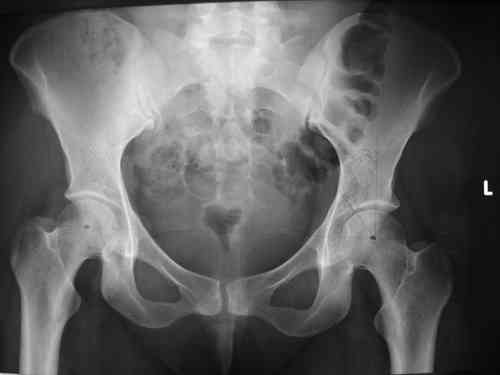

Спасибо за клинические примеры и комментарии. Если честно то просто восхищен представлеными R-ммами (классно сделали!!!). По поводу обсуждаемого больного: конечно КТ и дополнительные R-ммы сделаем. Но хочу напомнить, что после травмы прошло более 6 лет, на сегодняшний день клинически еще и R-ки признаки нестабильности эндопротеза( как бедренного компонента так и чашки). Хочется определиться как делать в аппарате или одномоментно открыто. Лично я склоняюсь к аппаратному лечению на первом этапе.

прилагаю пример с такой же давностью травмы, репонировали аппаратом

> в аппарате или одномоментно открыто. Лично я склоняюсь к аппаратному лечению на первом этапе.

задача непростая, если мало опыта в этом деле, подумайте еще раз